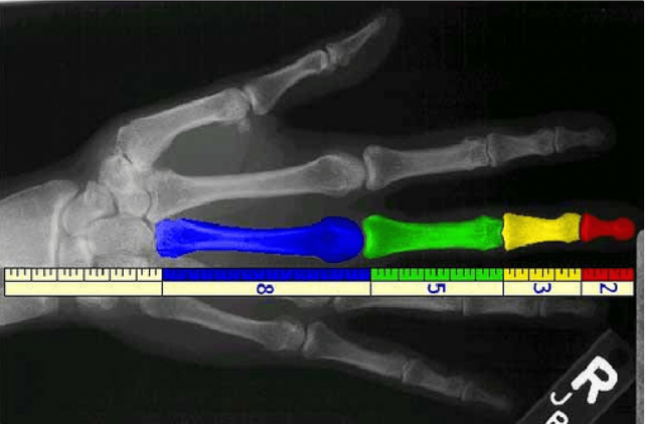

Thông thường thì 4 đốt xương của các ngón tay tuân theo dãy số Fibonacci: 2, 3, 5, 8. (Ảnh: Raciocínio Cristão)